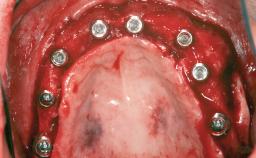

# of Implants 1

Type of Implants Two-Piece

Bone Augmentation Staged|Vertical